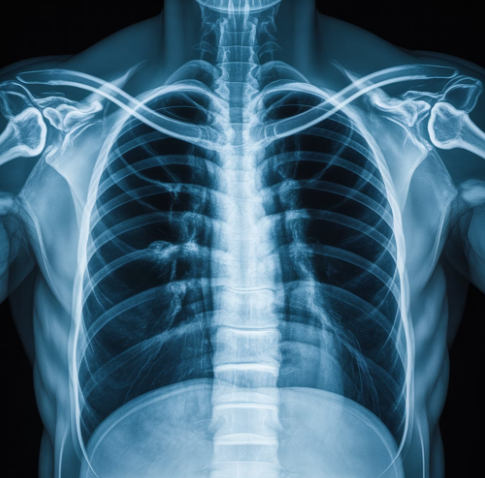

- 흉부 X-ray 검사 : 폐 안의 염증 범위를 확인

저는 감기라고 생각했는데, X-ray에서 염증이 보였을 때 정말 놀랐어요.